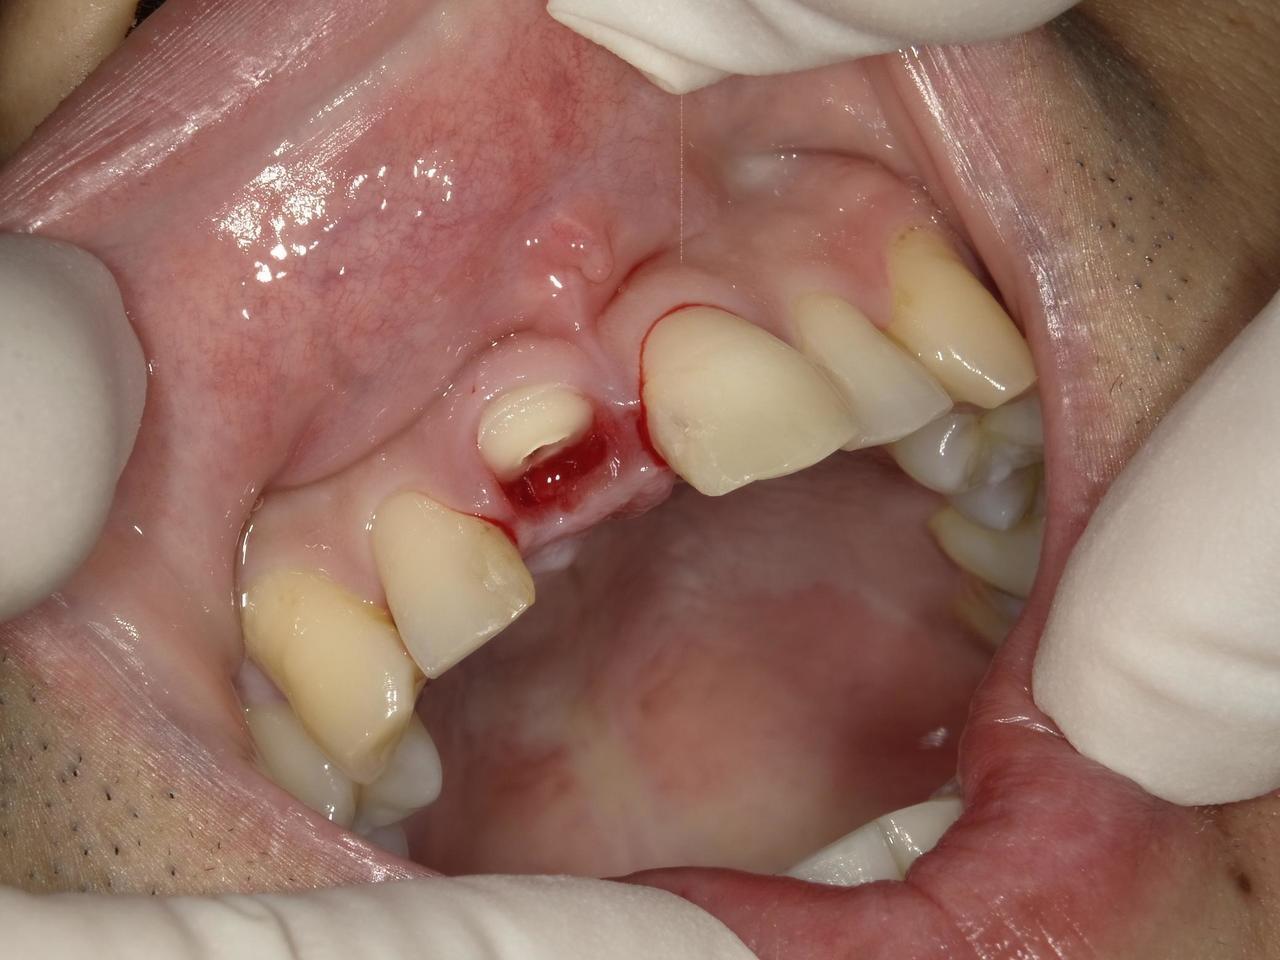

2.右上2番の前歯が、虫歯で折れてしまって、インプラント埋入当日に抜歯とインプラント埋入、仮歯まで装着して、2か月半で最終的な歯を入れたケース

術後の仮歯をつけた状態

K・Y 様 女性 50代

右上の2番3番がカリエスと食いしばりにより、破折したため、インプラント治療を希望

治療法としては、右上2番3番ともに、保存は、難しそうだったっが、患者様の希望もあり、右上3番は、歯を保存して、保険治療の前歯部のCADCAM冠で、どうしても残すことが無理であった右上2に関しては、インプラント手術、当日に抜歯をおこない、インプラント埋入をおこない、仮歯まで装着して、硬いものは、避けてもらうことを条件に食事ができる状態と歯がある状態で手術を終えました。その後、で2か月後にデジタル印象をおこない、2か月半で最終的なジルコニアの歯を入れ、治療を終えることができました。

治療の期間・回数:約2か月半、5回

治療の価格:404000円(税込)

治療費の内訳:インプラント基本料(フィックスチャー(ストローマン BLTインプラント使用)及び手術費用、投薬費用、レントゲン費用、インプラント上部費用(アバットメントおよびジルコニア)クラウンの費用用)360000円(税込み)オプション費用:抜歯即時埋入即時負荷加算(人口コツ費用を含む) 費用 44000円(税込み)

治療のリスクや副作用:手術後に、痛みや腫れ、出血、合併症などを引き起こす可能性があります。噛む感覚がご自身の歯と異なる場合があります。見た目がご自身の歯と異なる場合があります。手術後にメインテナンスを継続しないと、インプラントが抜け落ちる可能性があります。